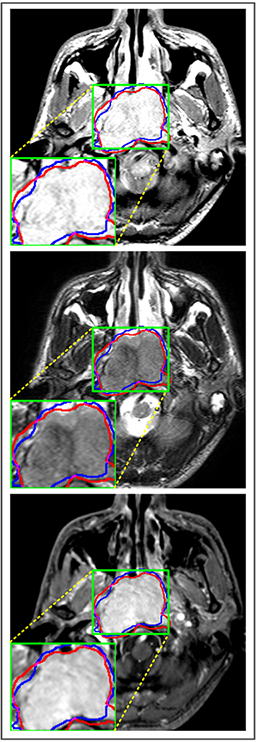

Refer to caption

(a) DSC=0.915

(b) DSC=0.870

(c) DSC=0.902

(d) DSC=0.898

Figure 7: Predicted results of proposed MMFNet in 2D images. There are corresponding T1, T2 and CET1 images from top to down. Boundaries created by radiologists are marked in red line, and the predicted boundaries are shown in blue line. The DSC𝐷𝑆𝐶DSC value is the dice similarity coefficient of this single slice.

Comparison with ground truth. Some predicted results of MMFNet are shown in 2D images and 3D images in Figure 7 and Figure 8. As shown in these figures, although the shape and size of NPC are varied from each other, MMFNet can still accurately determine the regions of NPC and obtain the accurate contours of tumors. Through analyzing 2D images in figure 7, MMFNet has a capacity to fuse multi-modality MRI to reduce the confusion brought by intensity’ similarity between nearby tissues and NPC. The values of meanDSC𝑚𝑒𝑎𝑛𝐷𝑆𝐶meanDSC, meanASD𝑚𝑒𝑎𝑛𝐴𝑆𝐷meanASD and meanHD𝑚𝑒𝑎𝑛𝐻𝐷meanHD of MMFNet are shown in Table 1. MMFNet can reach the best results with DSC=72.38%,meanASD=2.07mmformulae-sequence𝐷𝑆𝐶percent72.38𝑚𝑒𝑎𝑛𝐴𝑆𝐷2.07𝑚𝑚DSC=72.38\%,meanASD=2.07mm, and meanHD=18.31mm𝑚𝑒𝑎𝑛𝐻𝐷18.31𝑚𝑚meanHD=18.31mm.